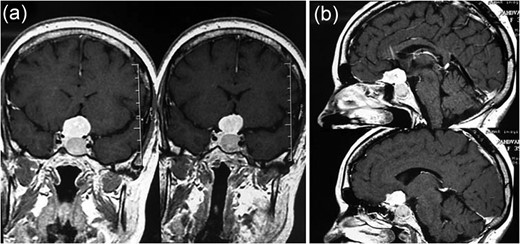

MRI showing (a) an intrasellar lesion isointense in T1W and T2W images enhancing homogenously and mildly after contrast material injection and (b) a suprasellar lesion 3 × 3 × 2 cm in diameter with the same intensity in T1W and T2W images which enhanced notably after contrast material injection.